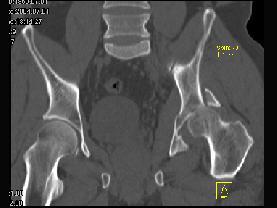

问题 男,44岁,有外伤史,请结合所提供的图像,选择最佳答案 ( )

选项 A、左髂骨骨折 B、左坐骨骨折 C、左髋关节脱位 D、左髋臼骨折并左髋关节脱位 E、左髋臼骨折

答案 D